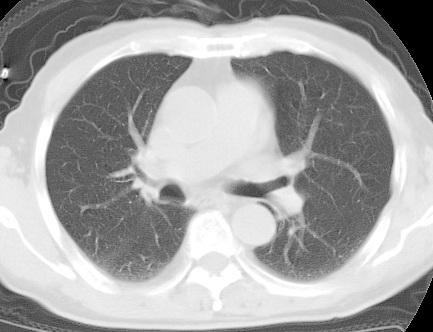

标题: CT24032:男65岁,咳嗽,吸烟20余年,无发热,咳痰 [打印本页]

标题: CT24032:男65岁,咳嗽,吸烟20余年,无发热,咳痰

考虑右肺中叶不张,请大家发表意见

中叶肺不张是没问题的,但为什么不在肺门区加薄扫呢?要查原因。

(有病变的地方应该薄层扫描,方便于诊断)

平片就可以诊断右肺中叶不张,做CT就是要找原因!中叶支气管开口不清,建议支气管镜检查。